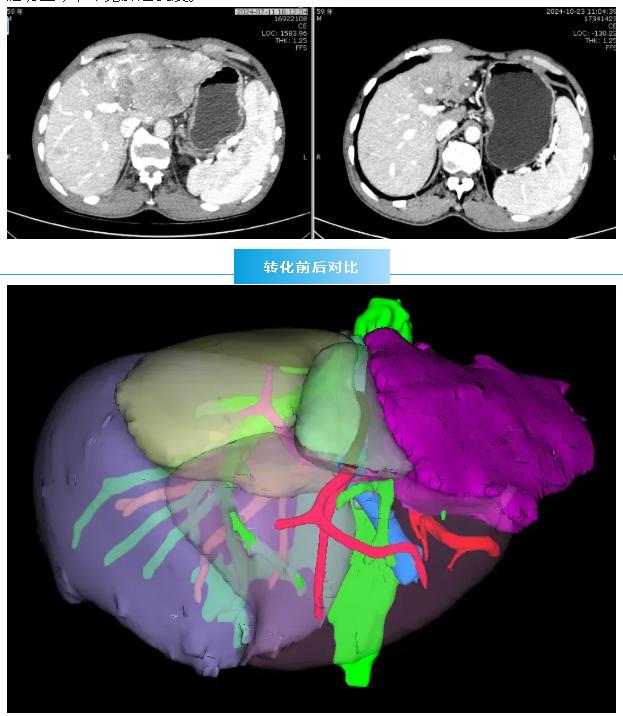

经过3个月的精心治疗,肿瘤显著缩小至约5cm×5cm,门静脉癌栓也明显退缩。再次经MDT团队评估,一致认为手术时机已然成熟。肝胆胰外科团队果断出击,成功为患者实施了 “扩大左半肝切除 + 肝7段结节切除”手术,实现了肿瘤的R0根治性切除。术后患者恢复顺利,随访至今,未见肿瘤复发。

术前3D重建

该患者为男性,有乙肝病史,体检发现左肝巨大占位(约15cm×8cm),右肝另有孤立小结节,更棘手的是,门静脉左支已出现癌栓并延伸至主干。临床分期为IIIa期,按CNLC指南属于潜在可切除肿瘤。面对困局,肝胆胰肿瘤诊疗中心迅速启动MDT。肝胆胰外科、肿瘤内科、放疗科、介入科、影像科等专家齐聚一堂,经过深入讨论,共同制定了周密的 “转化治疗”方案:先通过非手术手段将不可切除的肿瘤转化为可切除状态。